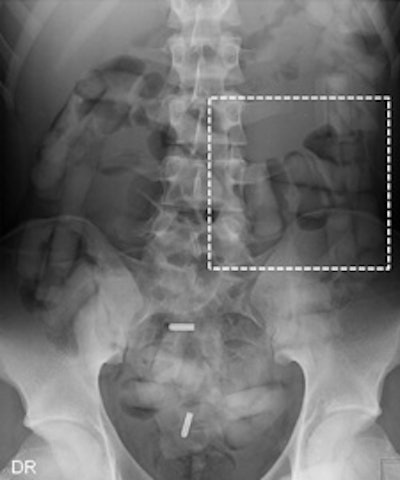

Top left: Low-dose linear slit digital radiography (LSDR) of a typical body packer with 145 intracorporal packs along the alimentary tract. Bottom left: Magnified view of the packs. Note the radiolucent rim within the periphery of the packs due to air trapping creating the so-called "double-condom sign" and "halo sign." Top right: DR of a typical body packer with 83 cocaine packs in the gastrointestinal tract. Bottom right: Note the longitudinal packs (weight approximately 10 to 12 g) projecting over the colon. The magnified view depicts the typical "double-condom sign" due to inevitable air trapped within the wrapping layers during manufacture.DR and low-dose linear slit digital radiography exams were less accurate. CT exams had an overall accuracy rate of 97.1%, followed by DR (71.4%, and 60% for low-dose linear slit digital radiography).

Capsules holding cocaine are of different densities. It is important to perform window-level adjustments to detect drug containers, according to the authors. It also helps for a radiologist to know what the typical size and appearance are of different cocaine containers. With this knowledge, they can be better distinguished from normal intestinal gas, calcifications, scybala, and other foreign bodies.